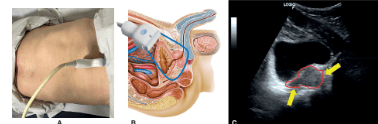

"ECOmécum, la herramienta fundamental para saber deecografía clínica." Con la llegada de los ecógrafos a los servicios de urgencia y atención primaria,resulta imprescindible formarseen su utilización yECOmécumserá la forma de conseguirlo. Orientado para la resolución de cualquier situación comprometida o duda en el diagnóstico ecográfico, este práctico manual, aporta lainformación necesaria en la clínica diaria; centrado especialmente en laecografía abdominal. Con un método sencillo y muy práctico, empieza por la base más fundamental y por unesquema de exploracióncon los cortes necesarios, posición del transductor, elresultado de la imagen ecográfica y la interpretación de la patologíahallada. Sin duda, una fórmula muy efectiva y rápida para el profesional, ya sea joven con poca experiencia o experto con necesidades de actualización en las nuevas técnicas.